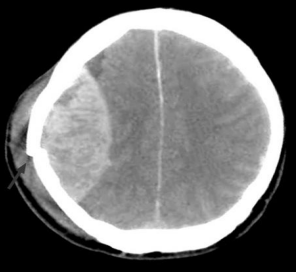

O trauma constitui uma das principais causas de mortalidade na Infância e adolescência, sendo o traumatismo crânio encefálico o trauma mais comum na infância.

Adolescente, 13 anos, vítima de atropelamento por carro, apresentou perda da consciência, logo após o trauma , mas ao chegar a equipe de resgate, a criança estava alerta, ECG de 14, apresentando intensa cefaleia e discreta hemiparesia à esquerda. Após 2 h na sala de emergência, apresentou rebaixamento do nível de consciência e piora neurológica. Foi submetida à TC de crânio de urgência.

De acordo com a imagem, o diagnóstico dessa criança é:

Fonte: Disponível em: <https://www.clinicadralexandrecruzeiro.webnode.com.br/news> Acesso em: 18 nov. 2017.